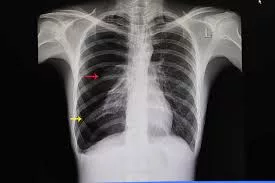

“Anaknya umur 10 tahun, kena tebuk paru-paru. Sekarang dipantau dekat hospital. Paru-paru dia dah lemah… dah dua kali operation.